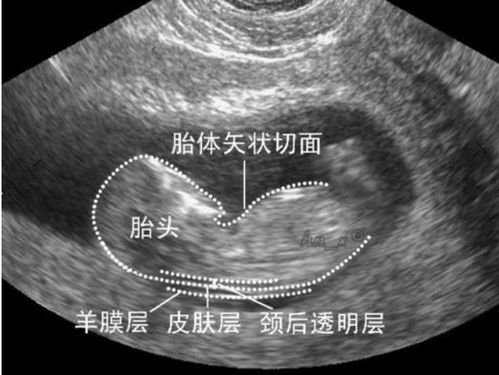

对于孕周与手术路径的选择,孕早期(0至孕吐之前,即孕三月末)通常可以选择人工流产术,此时的手术损伤相对较小。随着孕周的增加,进入孕中期后,可能需要考虑引产手术,这一过程相当于早产,风险也随之上升。孕晚期(孕二十八周之后)除非存在胎儿严重畸形等医学指征,否则应当尽量避免终止孕育。在任何阶段,做出决策前都必须进行全面的医疗评估。

政策规定,孕十四周内你有权自主决定是否终止妊娠。超过此周数则需要提供医学证明,如胎儿异常等。对于基于性别选择性的终止孕育行为,我们持坚决反对态度。在医院的流程方面,手术前需要完善一系列检查(如通过B超评估孕周),并签署手术同意书。涉及引产手术可能还需开具相关证明。